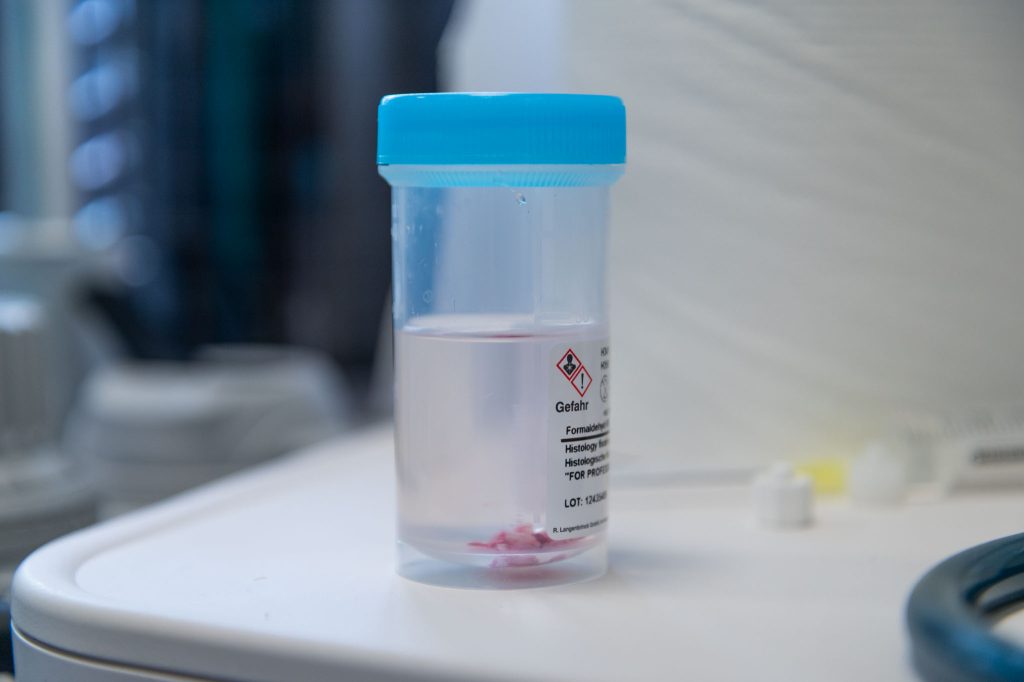

W trakcie diagnostyki możliwe jest pobranie:

Badanie histopatologiczne odgrywa kluczową rolę w rozpoznawaniu przewlekłych chorób zapalnych jelit, nowotworów oraz zmian o podłożu immunologicznym.